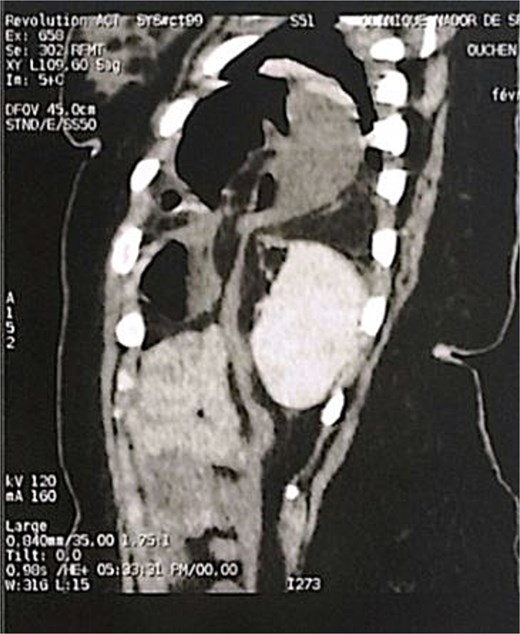

A 29-year-old female, with a history of cesarean section performed three months prior and no history of thoracoabdominal trauma, was admitted to the emergency department for an occlusive syndrome characterized by complete cessation of bowel movements and flatus, associated with vomiting, without other digestive or respiratory symptoms. On examination, the patient was conscious, haemodynamically and respiratorily stable. Abdominal examination revealed marked distension with epigastric tenderness, and digital rectal examination demonstrated an empty rectal ampulla. An initial plain abdominal radiograph, performed in the standing position and focused on the diaphragmatic domes, demonstrated colonic and small bowel distension with multiple air–fluid levels (Fig. 1). Subsequently, a thoraco-abdominopelvic CT angiography was performed, revealing a 3 cm left colonic herniation into the thoracic cavity through a partial posterolateral diaphragmatic rupture, associated with moderate left-sided pleural effusion (Figs 2–4). The herniation caused colonic stenosis at the diaphragmatic defect, with upstream distension of small bowel loops, the stomach remaining in its anatomical position (Fig. 5). These findings were consistent with acute intestinal obstruction secondary to a left-sided diaphragmatic hernia. Surgical management consisted of reduction of the herniated contents, assessment of their viability, and closure of the diaphragmatic defect using interrupted nylon sutures (sizes 2/0 and 0) (Fig. 6). Double drainage was instituted: a 28 Fr posteroinferior thoracic drain inserted through a dependent incision in the 5th intercostal space, and a Jackson–Pratt abdominal drain placed in the rectouterine pouch (Douglas’ pouch).

Sagittal section of an abdominal-pelvic angiogram showing a strangulated Bochdalek hernia with colonic and omental contents.